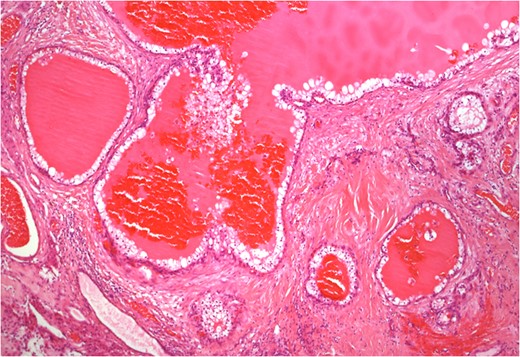

Histology of separate tumour deposit in testis composed of cystic spaces filled with eosinophilic secretions and lined by polygonal cells with clear cytoplasm (4× magnification).